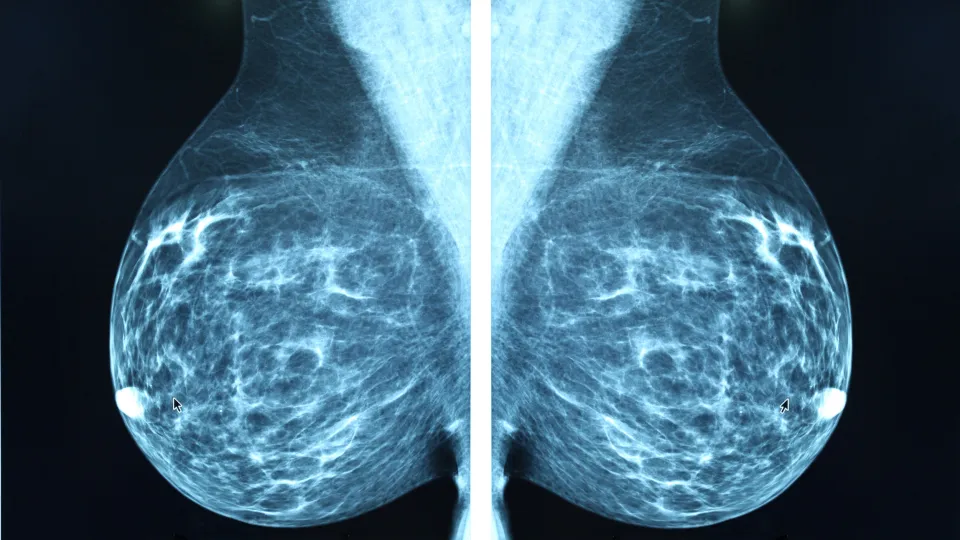

In Sweden, women between the ages of 40 and 74 are regularly invited to mammography screening. 106,000 women participated in the MASAI (Mammography Screening with Artificial Intelligence) trial. In previous reports from the trial, the research team had shown that the AI-supported screening method was safe and resulted in 29 percent more detected cancers, mostly small, lymph node negative invasive cancers. The strategy also made the screening more efficient since the screen-reading workload for radiologists was reduced by 44 percent (see links to previous news articles). By December 2025 all participants had completed a two year follow up.

For the individual woman participating in screening, there is no noticeable difference; the mammography examination proceeds as usual. It is afterwards, when the images are to be read, that AI support is used. In traditional screening, the mammograms are read by two breast radiologists, a medical speciality that is in short supply. In the MASAI trial, AI was used to triage mammograms to single or double reading based on AI risk scores. AI was also used as detection support for the radiologists where it marked suspicious findings in the mammogram.